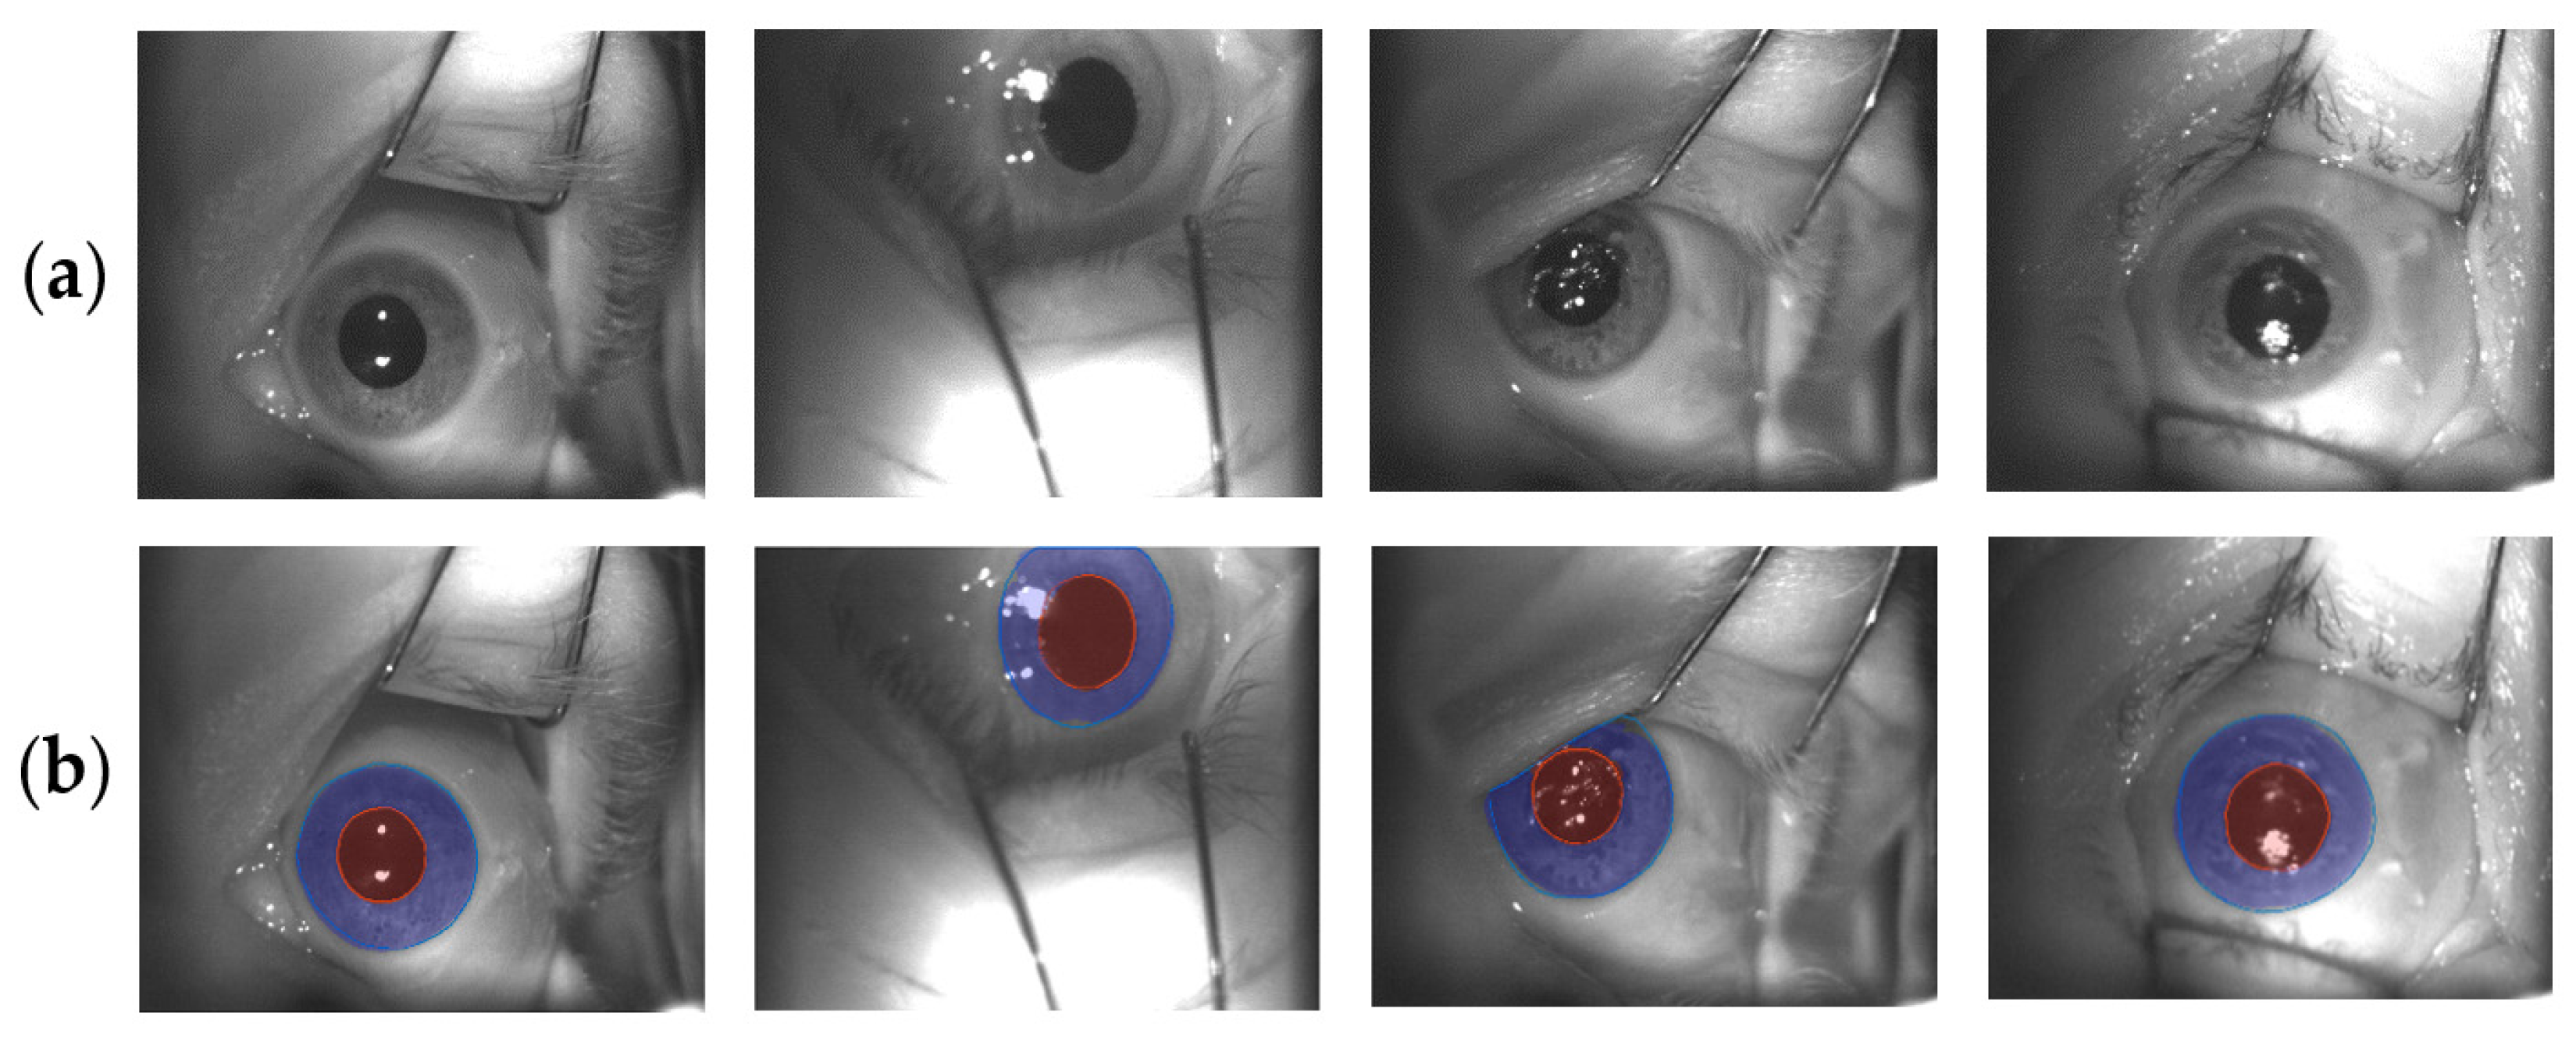

- Patient is immobilized on a treatment chair by using a personal thermoplastic mask;

- Eye retractors are placed to prevent eyelid movements and to maintain the eye wide open;

- Room illumination may be not homogenously diffused (this is a patient specific variable, since some of them are facilitated by low light conditions. ETS features two IR LEDs, resulting in insensitivity in those cases)

- Camera FOV is intrinsically not constant, depending by the desired gaze direction and the displacement of ETS in refer to the patient.